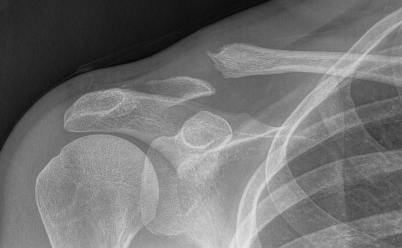

Neer Classification

Fracture lateral to the CC ligaments Non displaced

Fracture medial to the CC ligaments CCL ligaments attached to lateral fragment Medial fragment displaced superiorly |

Between conoid and trapezoid Conoid disrupted Trapezoid remains attached to the lateral fragment |

Lateral to CC ligaments Intra-articular extension Stable |

Periosteal sleeve disruption Pediatric Medial fragment displaced |

Comminuted Type II Medial fragment displaced |

Type I

Type II

Type V